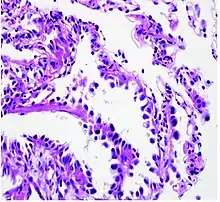

Histopathology

If possible, a biopsy of any suspected lung tumor is performed in order to make a microscopic evaluation of the cells involved and is ultimately required to confirm diagnosis.[7] Biopsy should be attempted in distant lesions first to establish a histologic diagnosis and to simultaneously confirm metastatic staging. The biopsy material is also used to analyze whether the tumor express any specific mutations suitable for tageted therapy (e.g. EGFR mutation or ALK mutation). Biopsy can be accomplished via bronchoscopy, transthoracic needle biopsy, and video-assisted thorascopic surgery (VATS).[4]

While sputum cytology has been shown to have limited utility, thoracentesis, or aspiration of pleural fluid with an ultrasound-guided needle, should be performed when pleural effusion is present. When malignant cells are identified in the pleural aspirate of patients highly suspect for lung cancer, a definitive diagnosis and staging (stage IV adenocarcinoma of the lung) is established.[4]

Adenocarcinoma of the lung tends to stain mucin positive as it is derived from the mucus-producing glands of the lungs. Similar to other adenocarcinoma, if this tumor is well differentiated (low grade) it will resemble the normal glandular structure. Poorly differentiated adenocarcinoma will not resemble the normal glands (high grade) and will be detected by seeing that they stain positive for mucin (which the glands produce). Adenocarcinoma can also be distinguished by staining for TTF-1, a cell marker for adenocarcinoma.[27]

As discussed previously, the category of adenocarcinoma includes are range of subtypes, and any one tumor tends to be heterogeneous in composition. Several major subtypes are currently recognized by the World Health Organization (WHO)[1] and the International Association for the Study of Lung Cancer (IASLC) / American Thoracic Society (ATS) / European Respiratory Society (ERS):[28][29][30] lepidic predominant adenocarcinoma, acinar predominant adenocarcinoma, papillary predominant adenocarcinoma, micropapillary predominant adenocarcinoma, solid predominant adenocarcinoma, and solid predominant with mucin production. In as many as 80% of these tumors, components of more than one subtype will be recognized. Surgically resected tumors should be classified by comprehensive histological subtyping, describing patterns of involvement in increments of 5%. The predominant histologic subtype is then used to classify the tumor overall.[2] The predominant subtype is prognostic for survival after complete resection.[31]

To reveal the adenocarcinomatous lineage of the solid variant, demonstration of intracellular mucin production may be performed. Foci of squamous metaplasia and dysplasia may be present in the epithelium proximal to adenocarcinomas, but these are not the precursor lesions for this tumor. Rather, the precursor of peripheral adenocarcinomas has been termed atypical adenomatous hyperplasia (AAH).[10] Microscopically, AAH is a well-demarcated focus of epithelial proliferation, containing cuboidal to low-columnar cells resembling club cells or type II pneumocytes.[10] These demonstrate various degrees of cytologic atypia, including hyperchromasia, pleomorphism, prominent nucleoli.[10] However, the atypia is not to the extent as seen in frank adenocarcinomas.[10] Lesions of AAH are monoclonal, and they share many of the molecular aberrations (like KRAS mutations) that are associated with adenocarcinomas.[10]